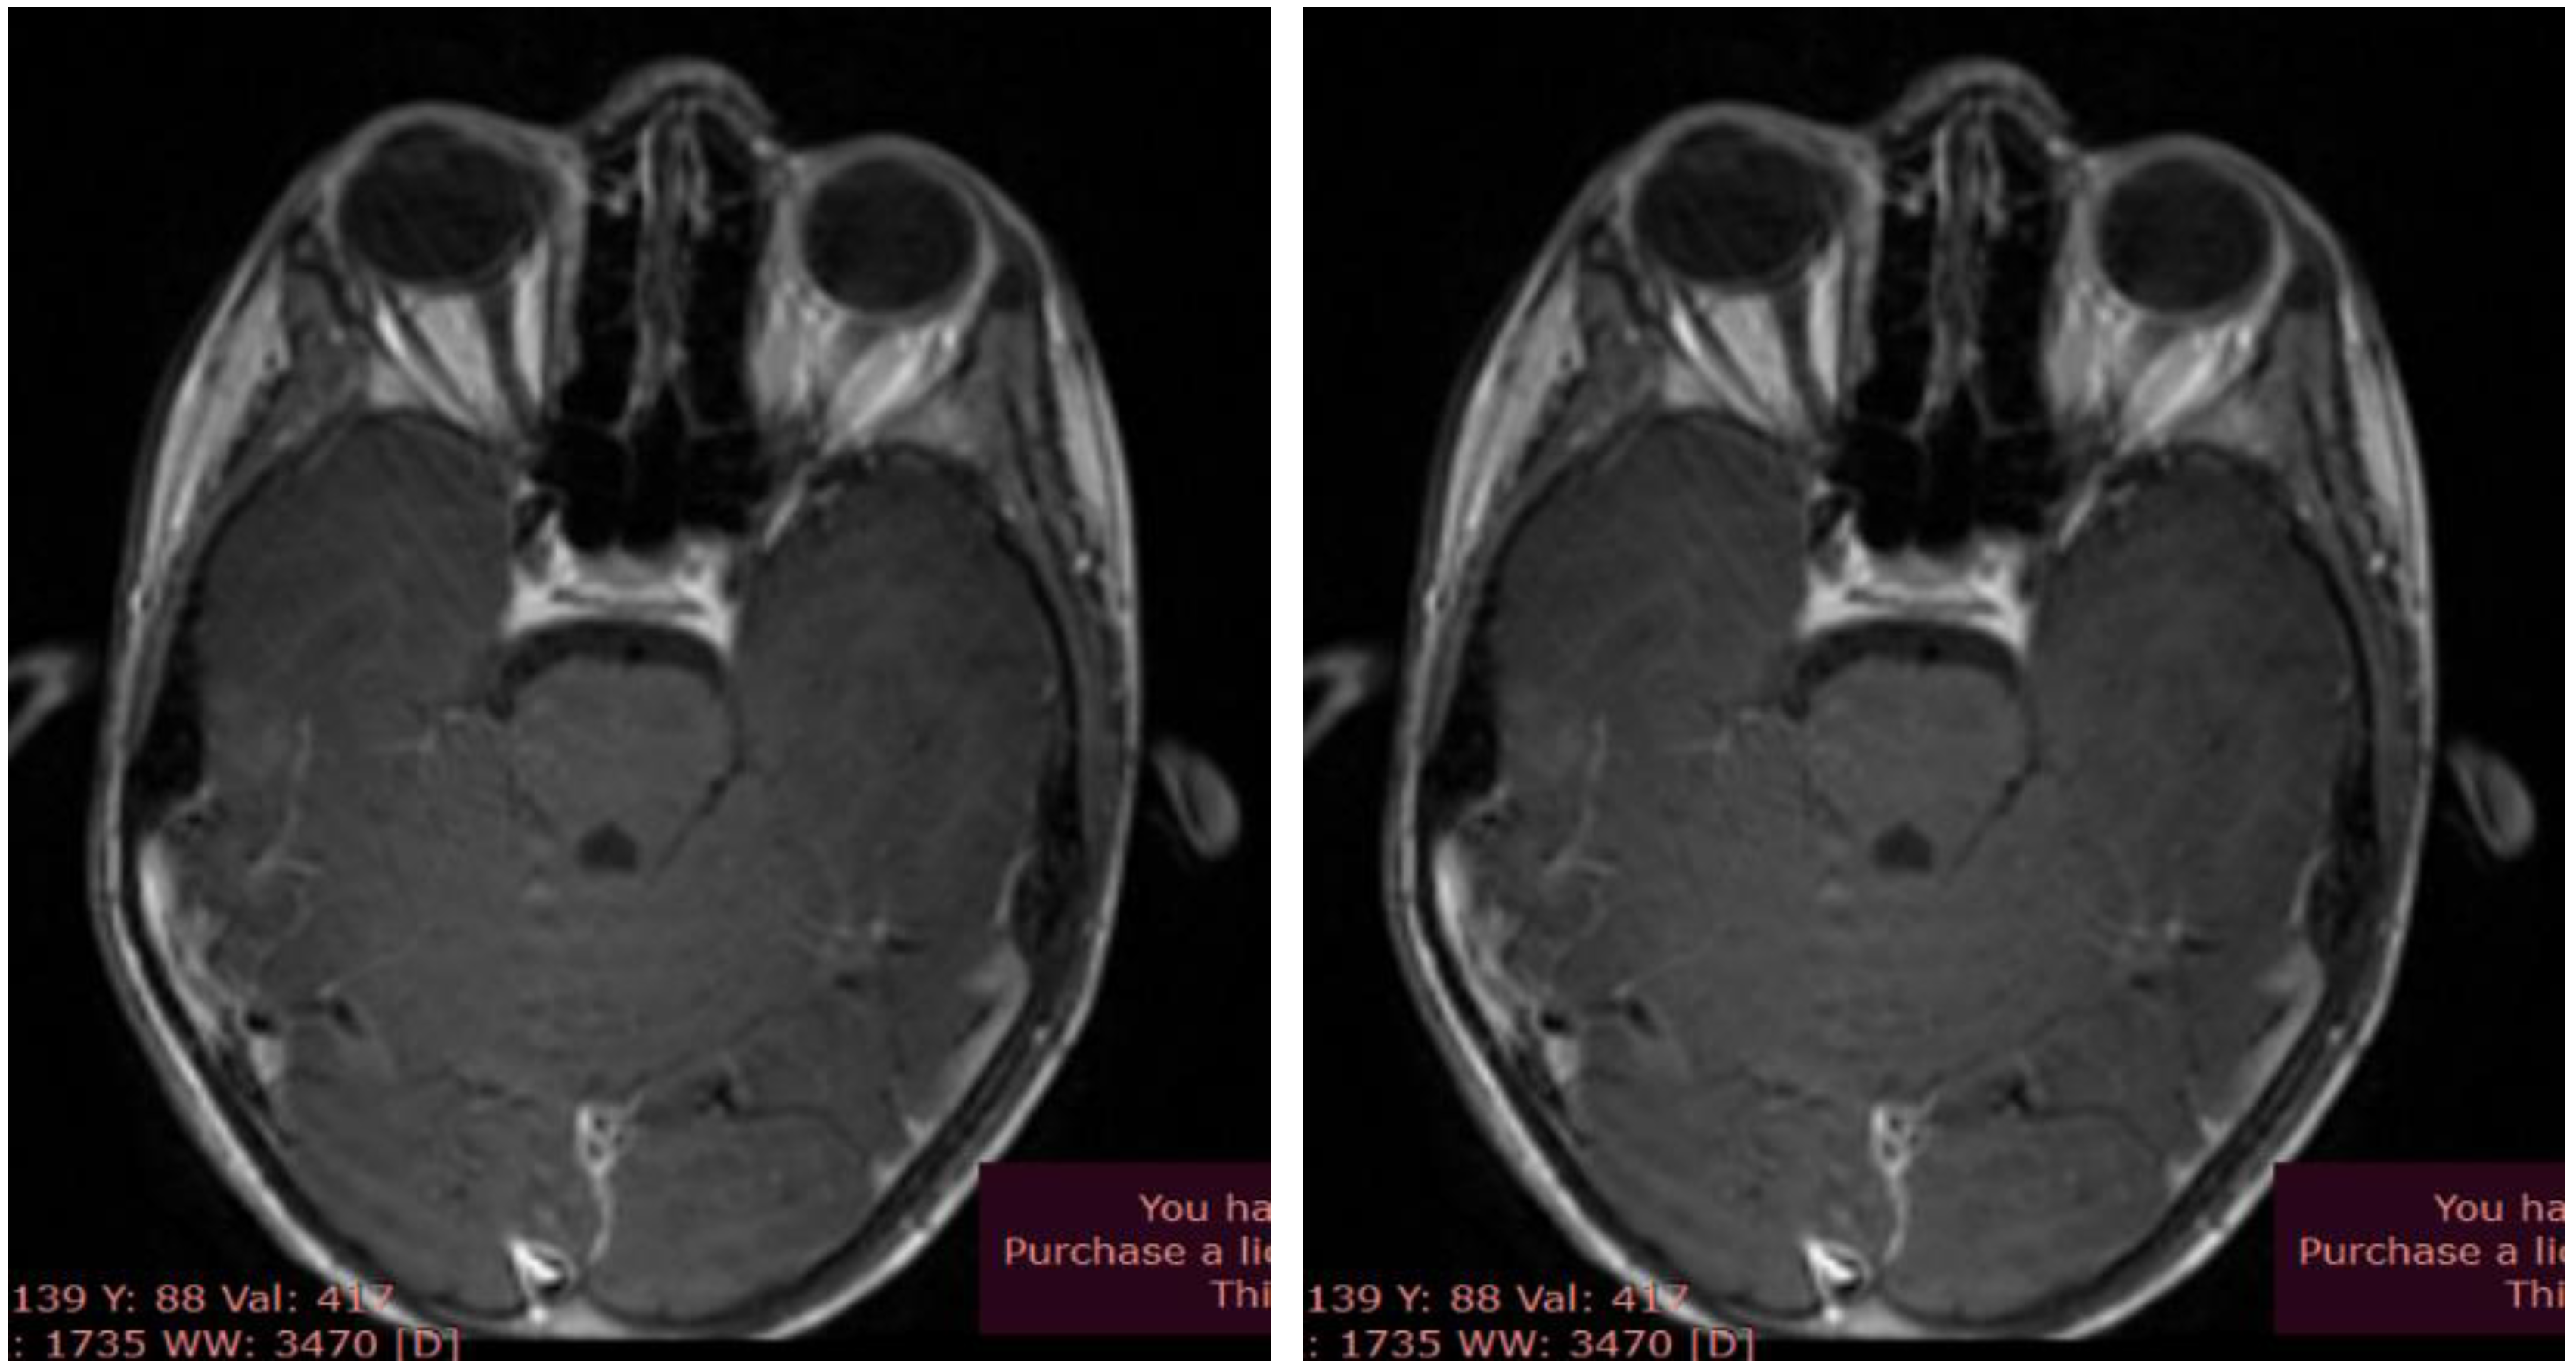

Cervical neck and brain MRI showed dimensional asymmetry at the level of the optic nerves (II), with a retro-ocular transverse diameter of 4.5 mm on the right side and 4 mm on the left side, but symmetric prechiasmatic areas, without native or post-contrast signal abnormalities. The imaging also revealed the existence of a retrovermian arachnoid cyst, paramedian on the left side with a diameter of 9/10 mm, and a minimal C5-C6 posterior disc bulge with discrete dural sac indentation, without discoradicular conflicts (Figure 2, A and B).

Figure 2. Brain MRI - optic nerves; (A) T2 sequence, native axial; (B) T1 sequence, axial contrast.